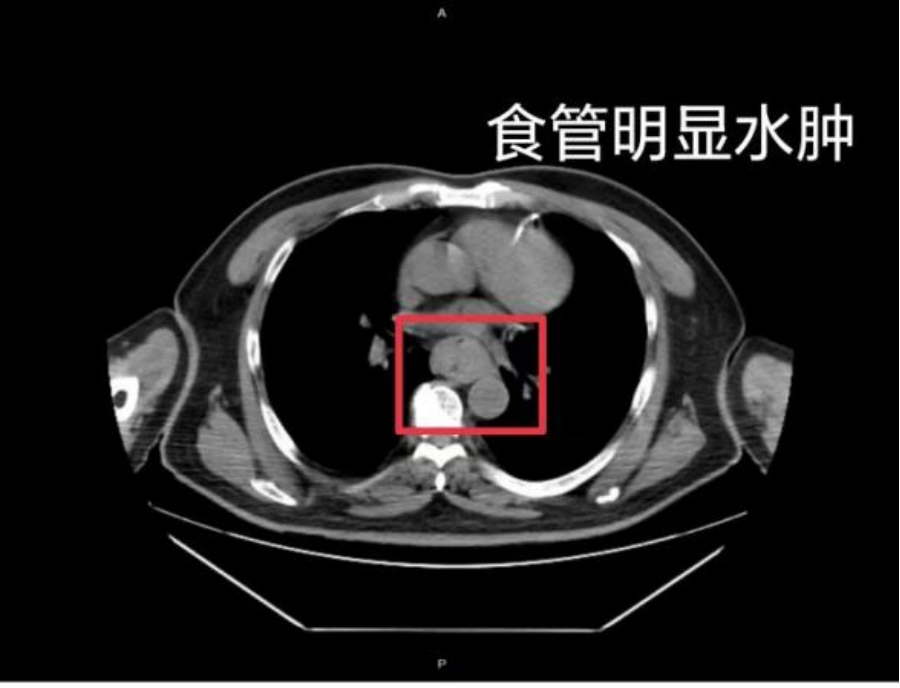

△图源:福建卫生报

据网友回忆,“自己去厕所尝试呕吐时,直接呕出了血,一大口鲜血从嘴里喷出,总共吐了两次。”CT结果显示,他的食管全部水肿损伤。